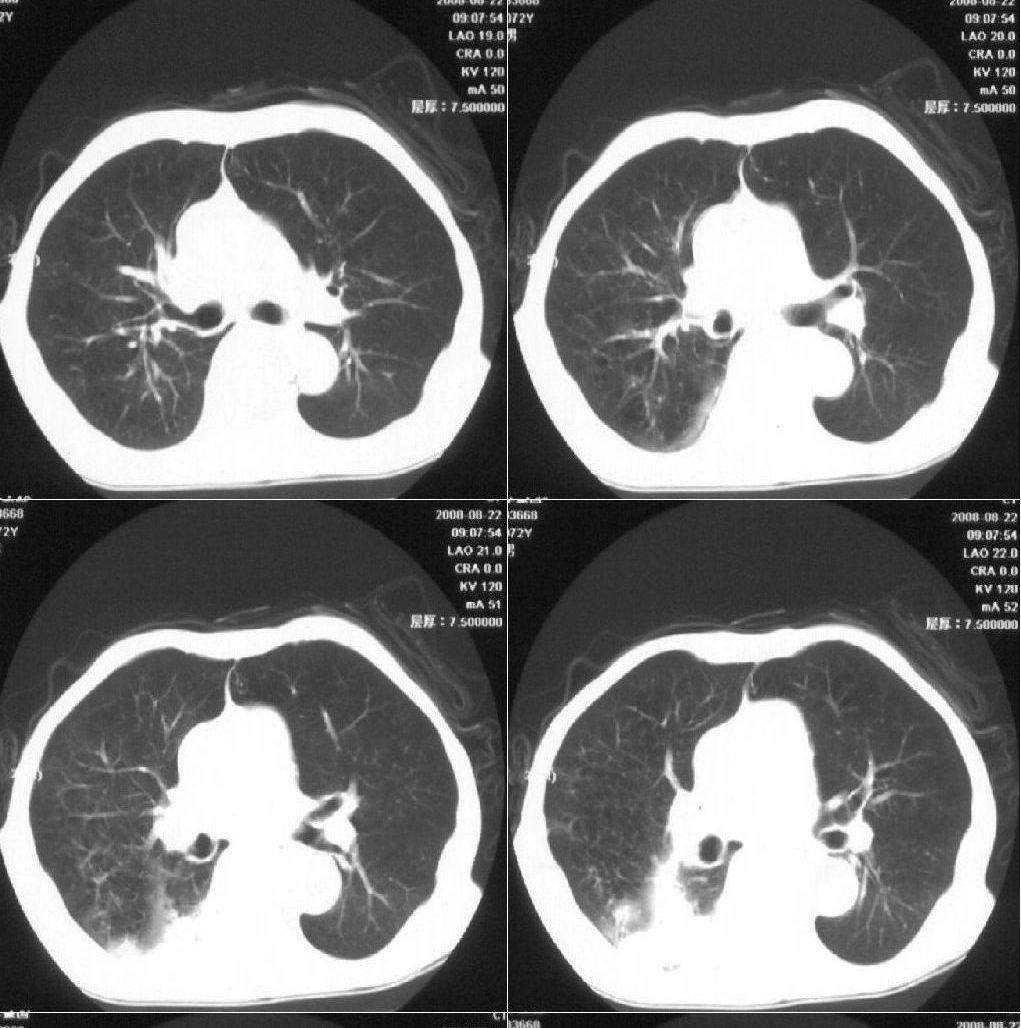

标题: 病例追踪

该患者通过抗炎治疗明显好转:当时患者消瘦,实是因为患者进食量不多。患者有食道癌,因发生原发肺癌的机率并不高,当时的ct片除了增强感觉有强化外(其实这信息也并不确定,因为是外院ct),其实并没有发现支气管腔改变等直接征象。经过治疗,患者现在一般情况良好。以下是9月22日的复查片,发现病灶吸收明显。纵隔窗就不上传了。

[本贴已被 fanshl 于 2008-9-26 10:52:11 修改过]